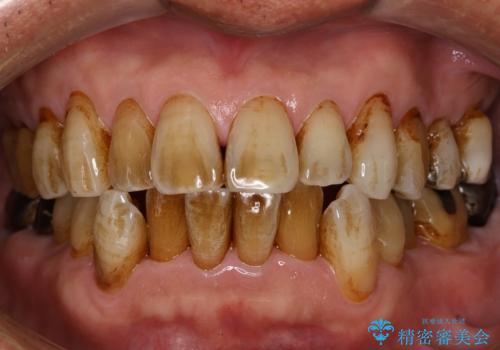

[ 虫歯・歯周病・インプラント ] 全顎補綴治療

![[ 虫歯・歯周病・インプラント ] 全顎補綴治療の症例 治療前](https://seimitsushinbi.jp/wp/wp-content/uploads/2025/08/70fb1789aa801a8616f6634871c40673-500x350.jpg?v=1754470286)